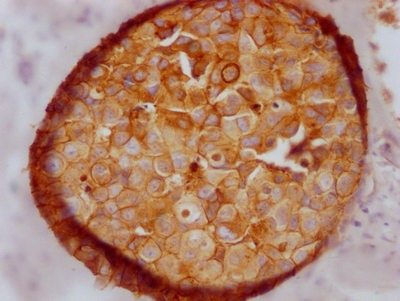

華美生物提供CDH1重組蛋白、抗體及ELISA試劑盒產(chǎn)品,助力您進(jìn)行相關(guān)機(jī)制研究及靶向藥物開發(fā)。